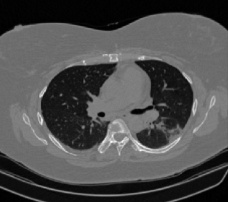

Figure 1 shows four CT scan slices, two from a non-COVID-19 CT scan, on the left and two from a COVID-19 scan, on the right. Bilateral ground glass regions are seen especially in lower lung lobes in the COVID-19 slices.